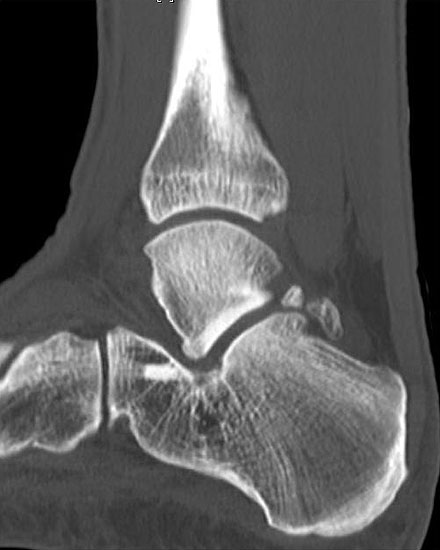

Abbildung Nr. 19-22

Knochenresektat sowie präoperatives CT (Sagittal- und Transversalebene) und intraoperative Bildwandlerkontrolle im seitlichen Strahlengang nach arthroskopischer Entfernung multipler Ossikel am dorsalen OSG/USG.